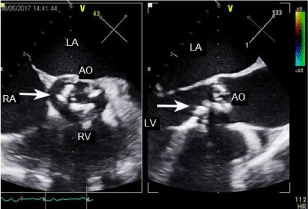

On the third day of the levosimendan treatment, the inflammatory parameters of the patient were rising, he became sub febrile. There was again a chance of infectious endocarditis. Transesophageal echocardiography (TEE) showed serious valve destruction with suspicion of rupture, aortic stenosis, aortic regurgitation (III-IV) and apposition referring to infectious endocarditis could be seen (Figure 1). The heart surgery consultation suggested that the patient should be taken to the cardiovascular surgery department where he was scheduled for operation. The patient was admitted on the next day.

Figure 1. Transoesophageal echocardiography. Arrows indicate calcified aortic valve. RV: right ventricle, AO: aortic valve, RA: right atrium, LA: left atrium.